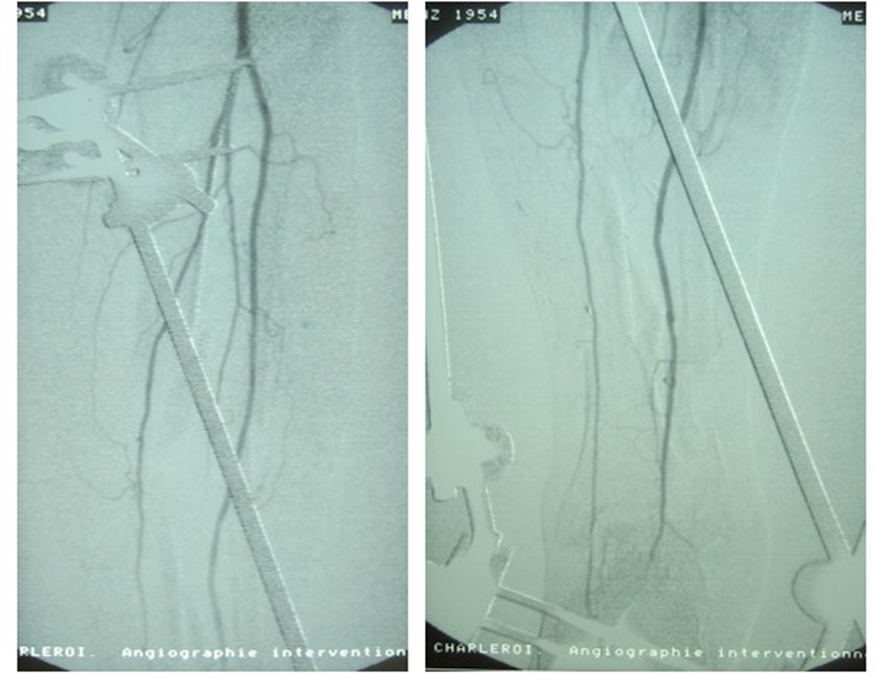

Figure 9, 10 : According to the angiogram of the traumatized leg, it was hazardous to perform a vascularized bone graft.